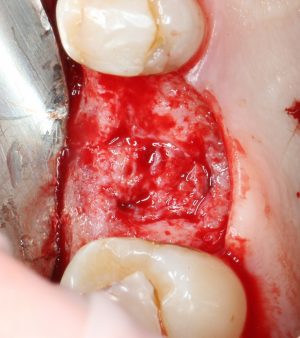

Начинаем подготовку лунки под имплантат

Далее, мы проходим лунку на всю глубину пилотной фрезой диаметром 2.0 мм.

После этого можно поставить пин и проверить направление и ангуляцию оси будущего имплантата.